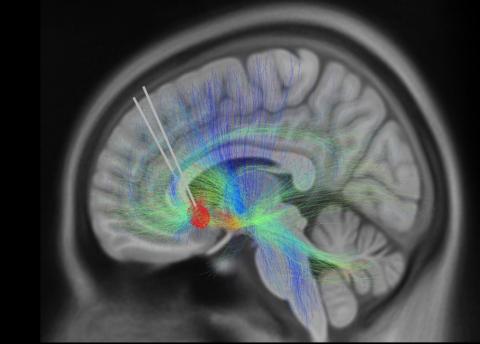

A brain image of twoimplanted DBS leads

Two implanted DBS leads, with nerve fibers extending into different brain regions. Biomarkers can help scientists track depression symptoms and optimize DBS techniques.

Photo:  KI SEUNG CHOI/MAYBERG LAB, ICAHN SCHOOL OF MEDICINE AT MOUNT SINAI